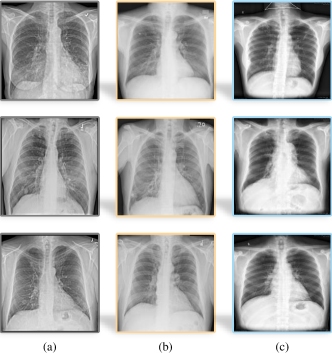

Refer to caption

Figure 1: Samples from multiple X-ray datasets: (a) NODE21 [27], (b) CXR [28], and (c) B-Nodule dataset, which is collected and annotated by ourselves. There exist certain domain differences among chest X-ray images from different datasets regarding illumination, color contrast/saturation, resolution, and nodule quantity.